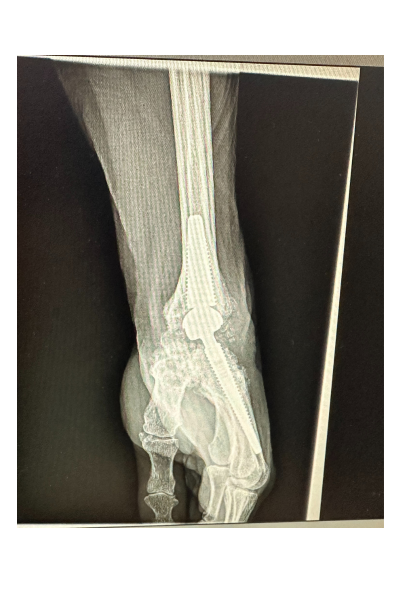

L’intervention nécessite un geste chirurgical précis dont la durée varie entre 1h et 1h30 et peut se réaliser en ambulatoire. Le chirurgien vient remplacer les os du carpe par une prothèse afin de restaurer une certaine mobilité articulaire.

Le poignet est une articulation complexe. Du fait du nombre important d’interlignes articulaires, cette zone est propice au développement de l’arthrose. Pour rappel, l’arthrose est synonyme d’usure du cartilage. Son origine varie, elle peut être dégénérative ou post-traumatique (séquelle de fracture ou d’entorse grave). L’arthrose peut également se développer dans le cadre de maladies articulaires inflammatoires (ex polyarthrite).

Ce concept de prothèse de poignet est une révolution en matière de prise en charge chirurgicale de l’arthrose. Conçue et largement répandue dans les pays nordiques depuis plus 15 ans, cette technique chirurgicale fait l’objet de plus en plus de communications au sein des congrès d’orthopédie français.